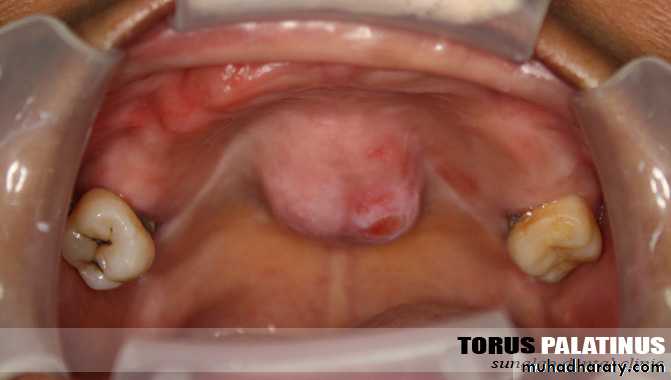

Palatal torus:

Small …ignore …relief

Same as mandibular indication

incisions:

Single midline palatal incision, Y, Horse shoe

Cut with fissure bur…..then use osteotome.. stent